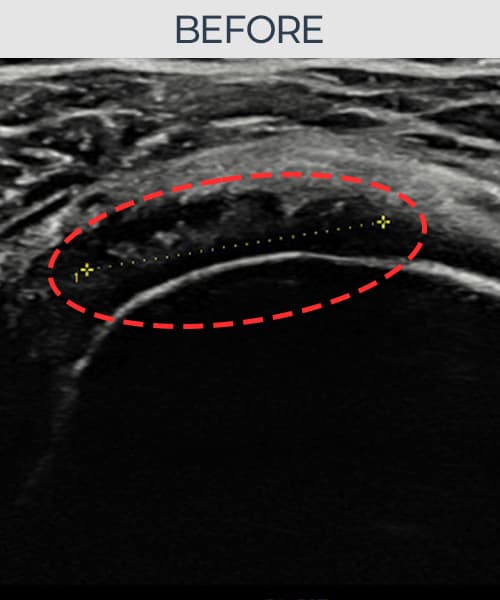

超声确认旋转肌腱袖 部分撕裂 + 韧带损伤(11mm × 6mm (肌腱厚度约58%缺损))。缩小缝合术后肌腱连续性恢复,患者回归正常生活。

术前

术前超声确认旋转肌腱袖 部分撕裂 + 韧带损伤,冈上肌腱回声不连续伴肌腱缺损(11mm × 6mm (肌腱厚度约58%缺损))。术后超声显示撕裂部位充满再生组织,肌腱连续性恢复,回声模式正常化。

该患者持续肩痛。详细超声检查确认旋转肌腱袖 部分撕裂 + 韧带损伤(缺损:11mm × 6mm (肌腱厚度约58%缺损))。在超声引导下实施非手术缩小缝合术。术后佩戴支具约4-6周,随后进行分阶段康复锻炼。随访超声确认肌腱连续性恢复、结构稳定,患者顺利回归日常生活。